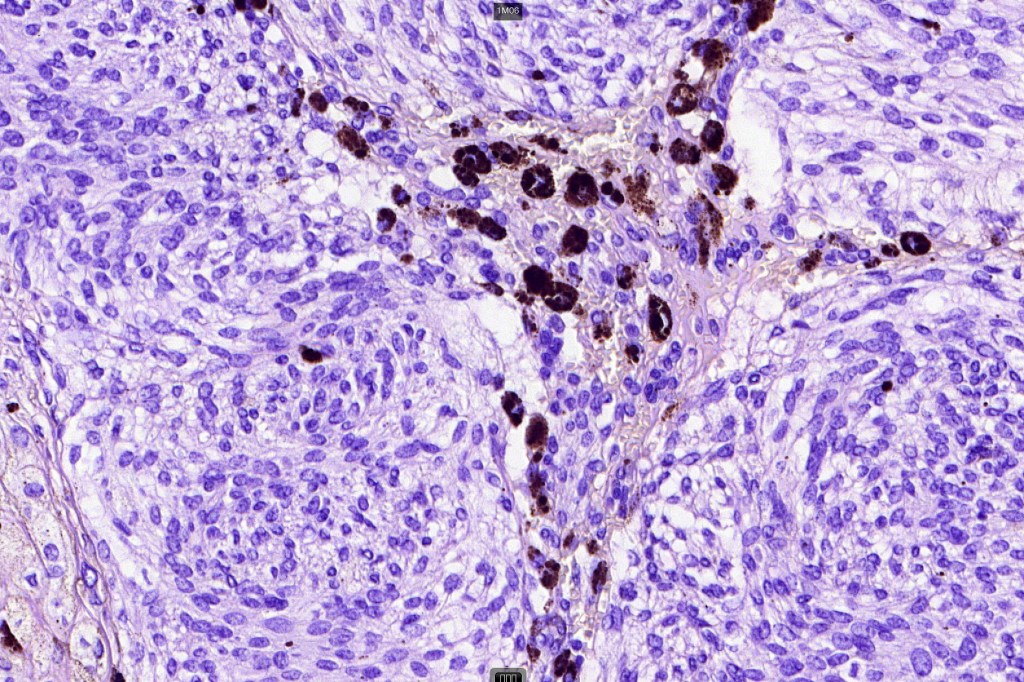

Histologically, it is characterized by a dense population of spindled, dendritic melnanocytes & melanophages with variable fibrosis. It may sometimes represent a component of a combined nevus. Mitotic activity is not usually present and pleomorphism is absent (see atypical blue nevus below). Involvement of the arrector pili muscle is not uncommon.

Very exceptionally, blue nevus also involves the epidermis (compound blue nevus).